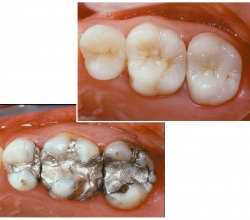

Inlays & Onlays